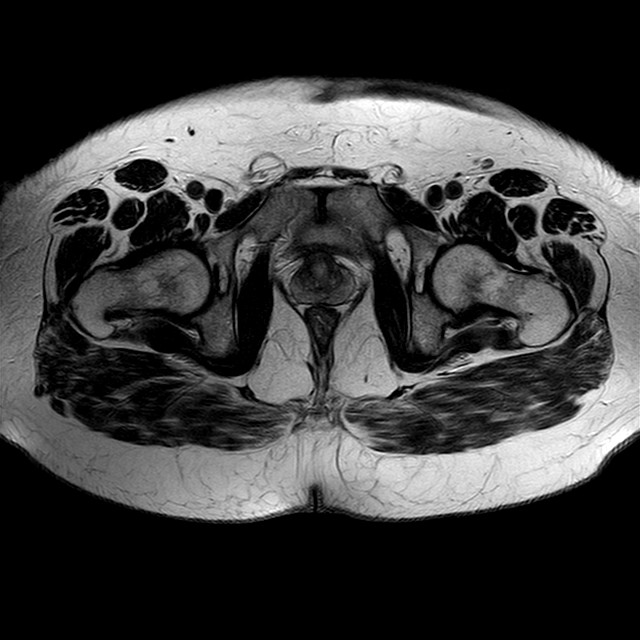

Esami: RMN BACINO

eT2w TSE

Evidenti e simmetriche alterazioni osteofitosiche in regione coxo femorale con riduzione delle rime articolari. Degenerazione completa del cercine glenoideo. Non attuali segni di versamento articolare. Non segni di edema osseo che escludono attuale algodistrofia od osteonecrosi. Lieve e simmetrica riduzione del trofismo della muscolatura glutea.